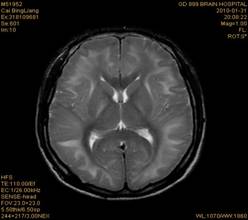

案例2 患者,女,30岁,二氯乙烷中毒性脑病的头颅MR。表现为双侧大脑半球皮层下白质、双侧外囊、双侧苍白球及双侧小脑齿状核内广泛片状、斑片状长T1长T2异常信号影,FLAIR序列呈高信号,增强后病变未见明显强化。

给予抗炎、脱水、疏通血管及营养神经等药物治疗。经过40天的对症治疗,痊愈出院。